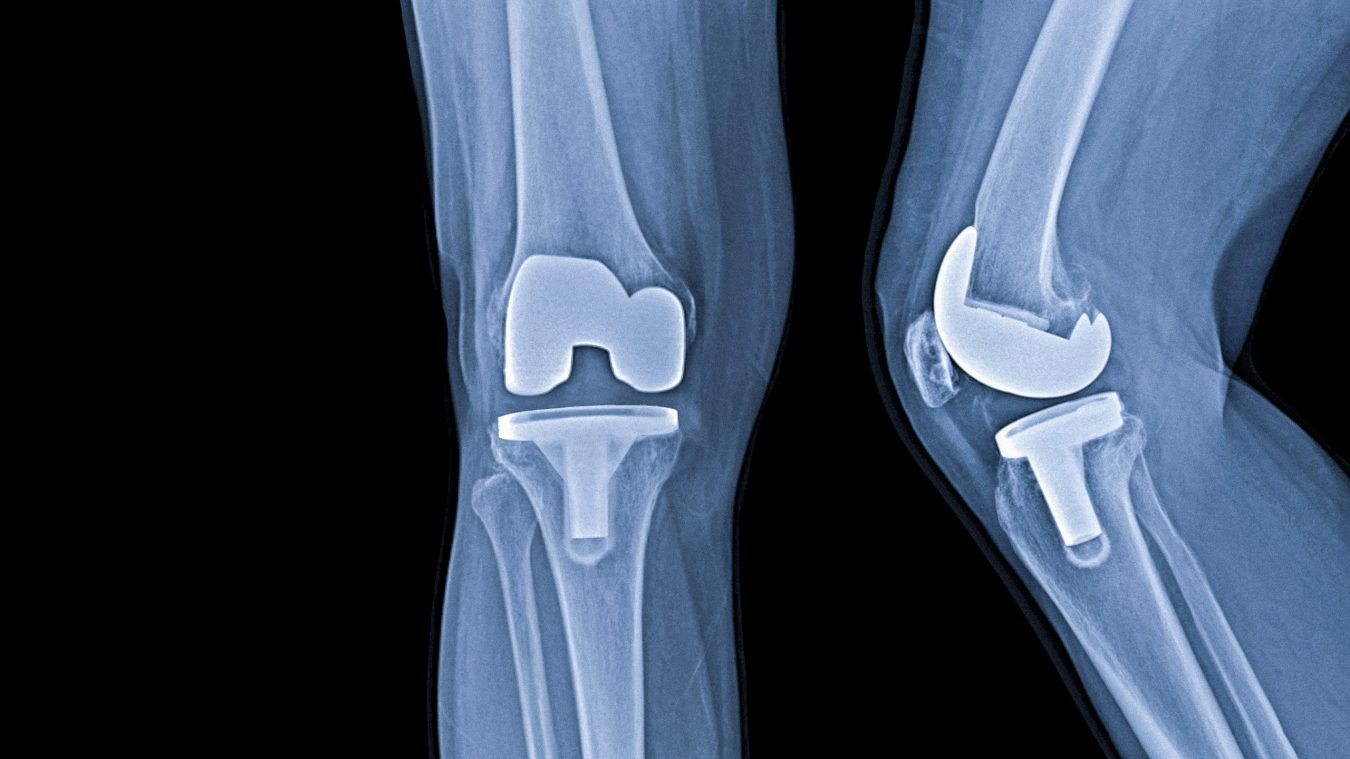

Heute gibt es eine Vielzahl Endoprothesenmodelle für Hüfte und Knie. Die Implantate sind dem natürlichen Gelenk nachempfunden, um einen harmonischen Bewegungsablauf zu ermöglichen. Um die hohen Belastungen zu kompensieren, bestehen Implantate aus sehr widerstandsfähigem Material: Kobalt-Chrom-Legierungen, Titan, Keramik und spezielle Kunststoffe, die eine sehr gute Gewebeverträglichkeit aufweisen. Bei der Wahl der richtigen Endoprothese berücksichtigen Fachärzte neben dem Zustand des erkrankten Gelenks individuelle Faktoren wie Körperbau, Knochenqualität, Lebensgewohnheiten, Gesundheitszustand, Alter und Geschlecht.

Das Knie ist das größte Gelenk des menschlichen Körpers. Ist das Kniegelenk nicht mehr intakt, schmerzt jede Bewegung. Die Folgen sind erhebliche Einschränkungen im Alltag.

Bei einem schweren, fortgeschrittenen Verschleiß, bei dem es zu einer hochgradigen Zerstörung der Gelenkflächen gekommen ist, ist der Einsatz eines künstlichen Kniegelenkes meistens unumgänglich und Kniechirurgie erforderlich. Zu unserem Leistungsspektrum gehören: